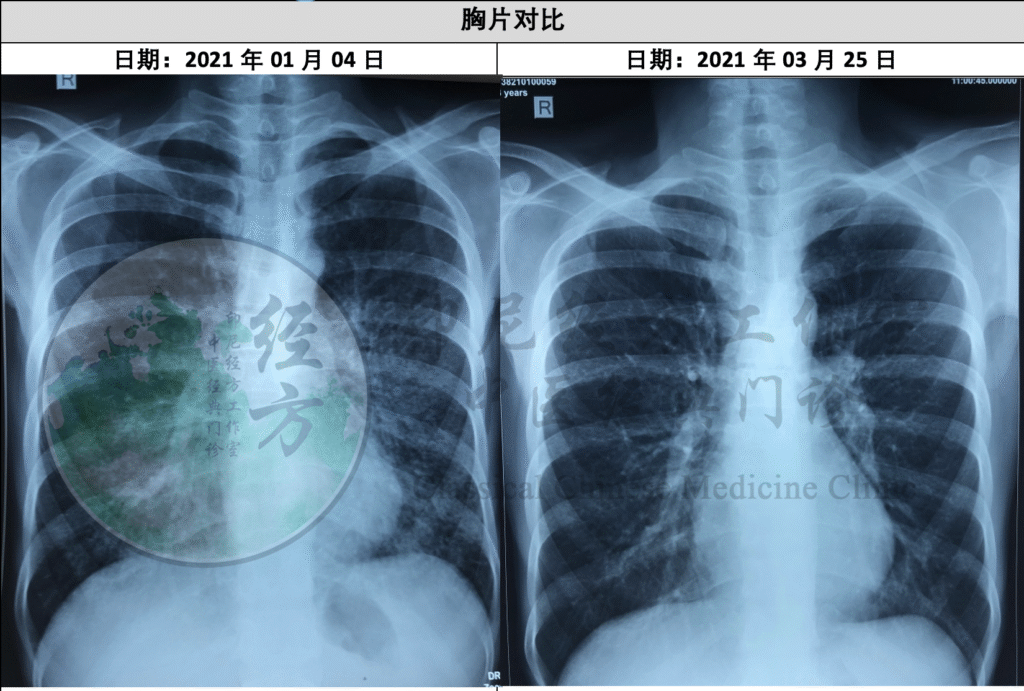

Pada kunjungan kelima (17 April 2021), hasil rontgen paru (25 Maret) menunjukkan perbaikan yang sangat jelas dengan berkurangnya infiltrasi pada paru-paru. Berat badan pasien meningkat lebih jauh menjadi 46 kg. Terapi dilanjutkan dengan Chai Pu Tang dan Xie Xin Tang untuk mempertahankan tren pemulihan.

Rontgen paru:

4 Januari 2021: infiltrasi luas

25 Maret 2021: infiltrasi berkurang nyata

Perbaikan sesuai peningkatan berat badan dan energi.